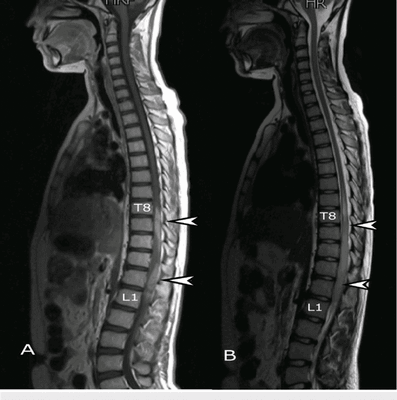

Основные отличия МРТ от КТ позвоночника кроются в принципе получения изображения. Современная компьютерная томография (или МСКТ - мультиспиральная компьютерная томография) основана на способности по-разному, в зависимости от плотности тканей, поглощать рентгеновское излучение. Особенности мультиспиральной компьютерной томографии позвоночника заключаются в том, что в ходе процедуры собираются множественные непрерывно перекрывающиеся срезы. Это дает возможность производить компьютерную обработку данных с последующим созданием объемных, так называемых 3D изображений и реконструкций. Полученные на МСКТ позвоночника снимки врачи могут рассматривать на экране с любой стороны как в режиме индивидуального просмотра, так и в режиме анимации, когда объект вращается вокруг своих осей. Используя специальные функции разворота и обрезки, можно выделить интересующую область и визуализировать ее с любой стороны. Это дает возможность медикам видеть скрытые структурные повреждения.

Послойное исследование спины с помощью КТ позвоночника позволяет обнаружить такие патологии, как:

- компрессионные переломы, травмы и трещины костей;

- рак и метастазы в костях;

- стеноз позвоночного канала;

- остеофиты и признаки остеопороза;

- опухоли костей - остеохондрома, энхондрома, хондробластома, остеоидостеома, миелома.

МРТ позвоночника дает возможность хорошо визуализировать спинной мозг, мягкие ткани, грыжу межпозвоночного диска. В случаях, когда неврологам, травматологам и хирургам необходимо получить трёхмерную реконструкцию и исследовать кости позвоночника в разных плоскостях или диагностировать обызвествление межпозвоночного диска, применяется КТ позвоночника.